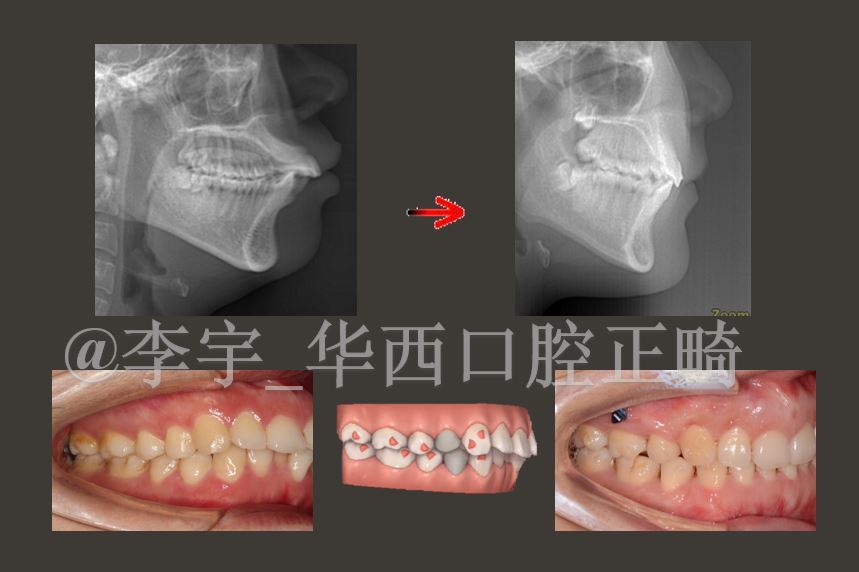

本年的“隐适美”专场共邀请了国内外14位隐形矫治的尖端专业的人介绍自己的经历和诀窍。我讲演的主题是“IMSAS攻略之支抗钉用于前突矫治”。“IMSAS”是我提出的通明牙套矫治系统化攻略,已在全国讲演十余场,并写入了专著。前突病例是隐形矫治的难点。我别离叙述了运用支抗钉进行前突病例拔牙矫治、推磨牙矫治,以及严峻骨性II类代偿医治的关键。

在大会同期还在上海举行了隐适美青少年隐形矫治Teen-edge项目季度会。作为全国12名Teen-edge导师之一,我受邀做了关于青少年下颌后缩前期隐形矫治的专题讲演。